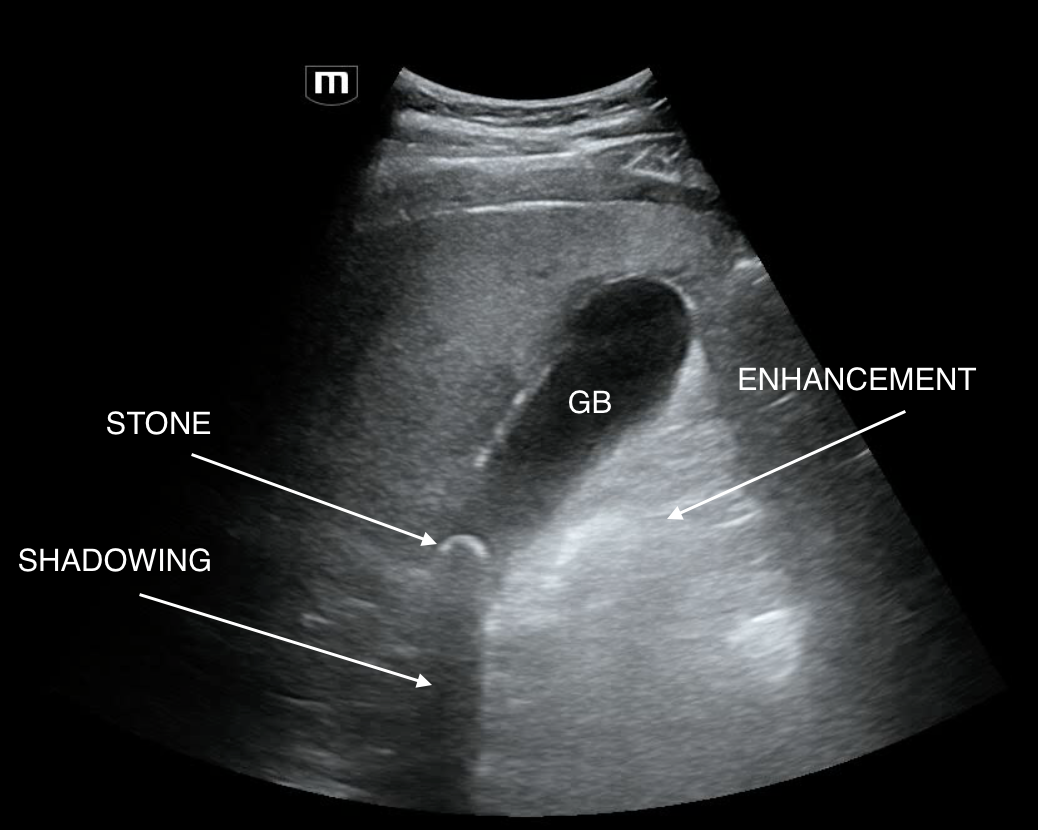

Stills annotated below to show the features of cholecystitis

So, when you see a stone impacted in the neck of the GB, sit the patient up or roll them to L lateral decubitus to see if the stone moves to the fundus. If it does not as in this case: it's impacted.

The most sensitive features of cholecystitis for EDUS are seeing a GB stone and eliciting sonographic murphey's sign.